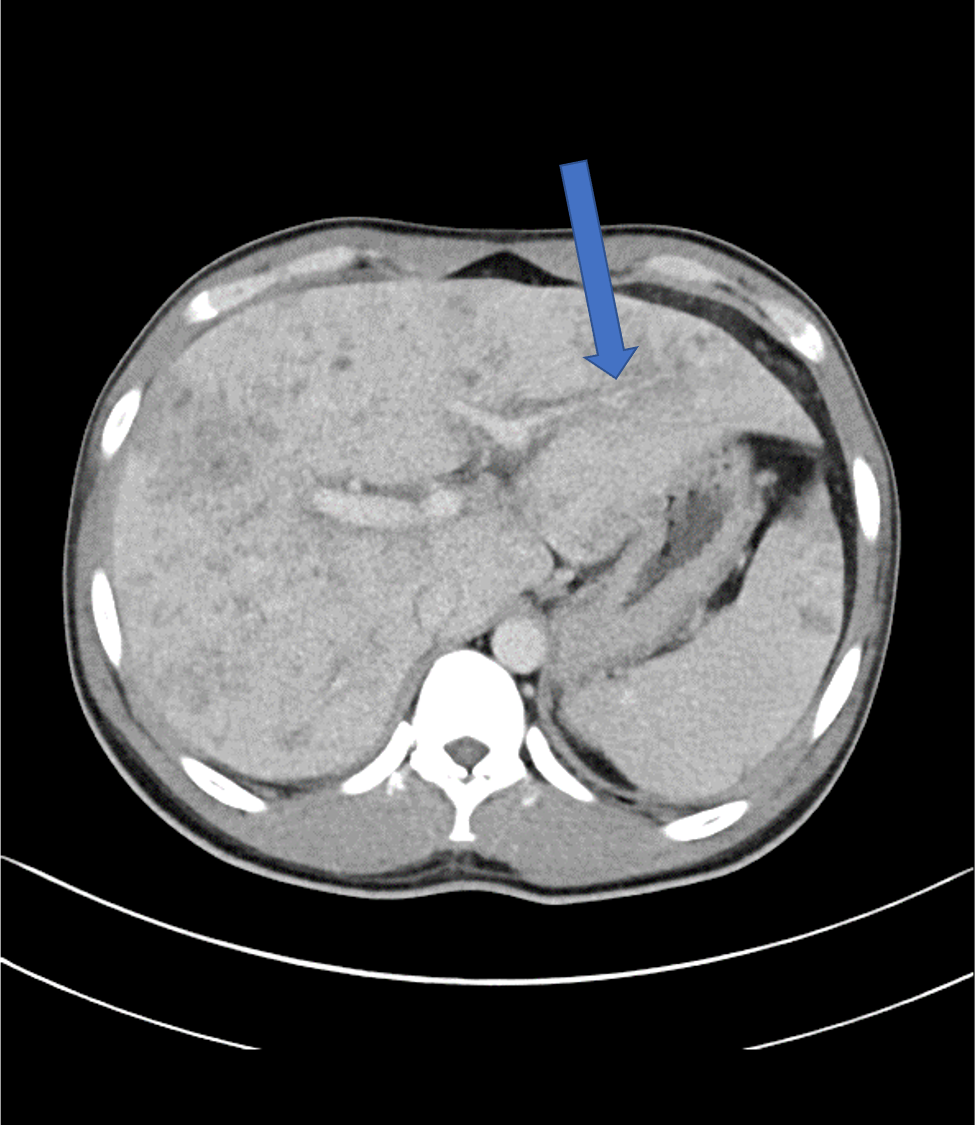

肝内に地図状の乏血性の領域や、病変内に門脈枝の貫通像がみられ、これらは好酸球増多症における肝病変として矛盾しない所見であった。

動脈相では乏血性の領域が見られ、門脈相では最もコントラストが強まる。平衡相では遅延性濃染がみられる。本症例はこれらの所見に合致した。

またperiportal collar signを捉えやすいこともダイナミックCTを撮像する利点である。

そして本症例でも見られているが、病変内に門脈が貫通する所見が好酸球増多症における肝病変として特徴的であり、これを門脈相で捉えられることもダイナミックCTを撮像する利点である。